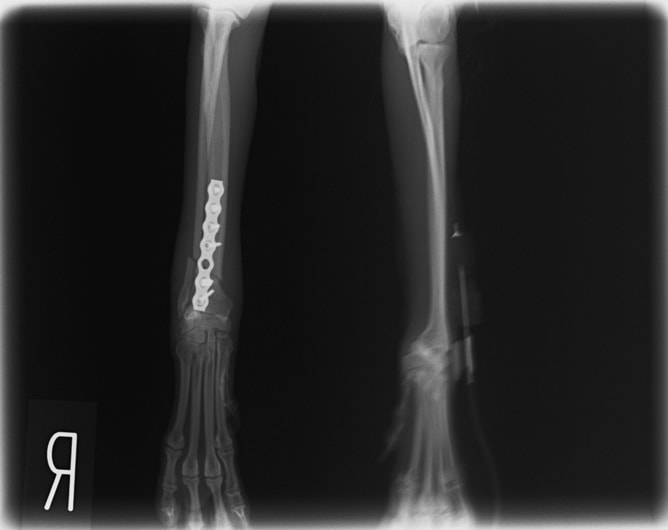

トイプードル 右遠位橈尺骨短斜骨折のALPSによる内固定

当院ではAdvanced Locking plate system(ALPS)と、Locking compression plate system(LCPS)という骨接合法で骨折症例の治療を行っています。

LCPは、スクリュー(ネジ)とプレート(金属の板)をロックする特殊な構造により骨折部位を固定する新しい世代のプレートシステムです。ひとつのホールでロッキングスクリューとスタンダードスクリューの使用を選択できるユニークな構造をしているため、骨折断端間の圧迫を目的とした従来型プレート固定法に加え、高い角度安定性を有するロッキングスクリューを用いた固定法の選択が可能です。従来のプレートシステムでは困難だった部分の骨折や癒合不全の症例に高い治療効果をもたらします。

1.骨膜上の血行障害は最小限

2.高い角度安定性

3.プレート設置時の整復位喪失の防止

4.スクリューのルースニング(ゆるみ)の防止

5.コンビネーションホール

6.粗鬆骨における固定性の向上

7.1.5mmと薄いプレートのため、超小型犬にも使用しやすい

8.抜去が不要となることが多い